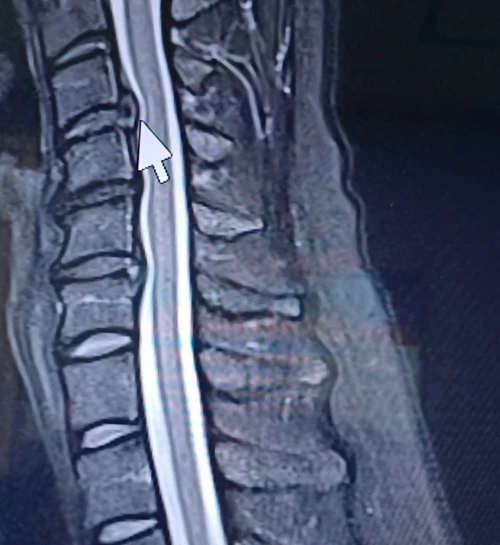

꼬리뼈는 그간 치료 덕인지 아니면 목 통증이 더 강해서인지 잘 느껴지지 않았다. 결국 CT는 찍지 않았다. 영상을 설명하던 의사는 화살표를 가리키며 말했다.

“원래는 추간판 탈출증인데, 일자목이라고들 하죠. 좀 심하네요. 수술이 필요할 수도 있어요. 자세한 건 정형외과나 재활의학과에서 상담해 보세요.”